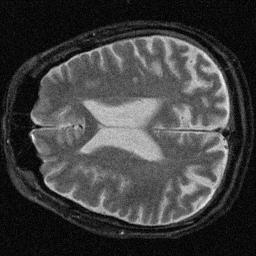

The resolution loss is measured relative to the FWHM of the noisy image, consequently its resolution loss is 0%. Interesting is that the CNR mirrors changes in the SNR, as expected. Also interesting is that the contrast filter reduced the SNR dramatically while actually improving the image resolution. The following images were obtained after filtering:

Noisy Image